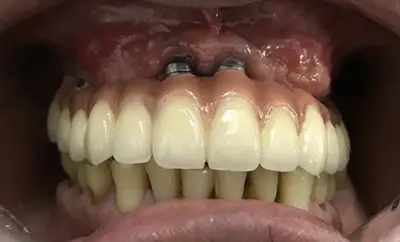

Case 4: Maxillary Hybrid Denture